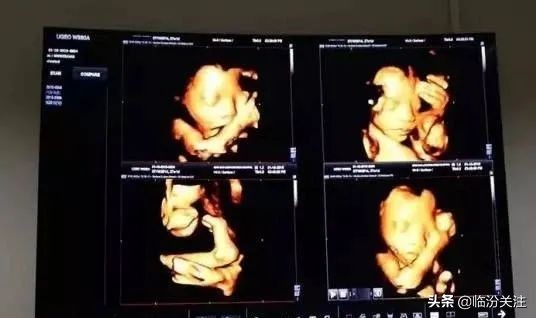

五維彩超除了能讓準爸媽提前跟未出生的寶寶“見面”,它最主要的功能是多方位、多角度地觀察宮內胎兒的生長髮育情況,精準、便捷的早期排查寶寶畸形和不良發育的情況,減少出生缺陷。另外,五維彩超的影象顯示更清晰、更準確。因此,為了孕婦和胎兒的健康,產檢選擇做五維彩超檢查非常有必要。

這是胎兒醫學排畸最關鍵的一個階段。五維彩超是孕期至關重要的檢查專案,它能觀察寶寶的外貌形態、生長髮育等情況,為寶寶健康保駕護航。另外,還可以記錄下寶寶在胎兒時期的模樣,賣萌的、吃手指的、啃腳丫、打哈欠、噘嘴巴的各種可愛的小動作,簡直萌翻啦。

❷ 五維彩超 · 家屬也可陪同孕媽媽躺上床等孕肚上塗上耦合劑後,便可開始檢查了。醫生會耐心地講解胎寶的發育情況,家屬也可以貼心陪同孕媽進行檢查,透過觀診屏,家屬可以和孕媽媽同步看到超聲影像哦。和寶寶say hello!